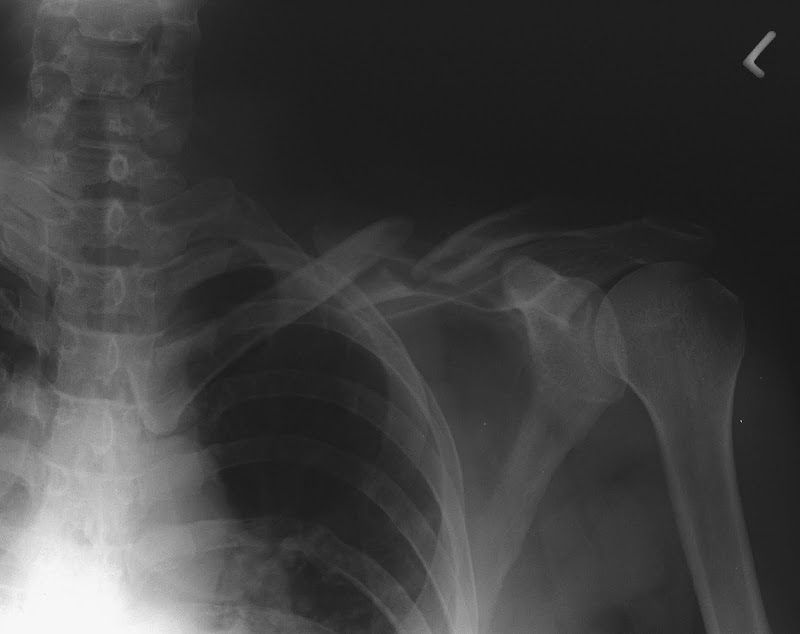

- Knochenbrüchen (insbesondere offene),

Link: Der kleine Lebensretter: Knochenbrüche